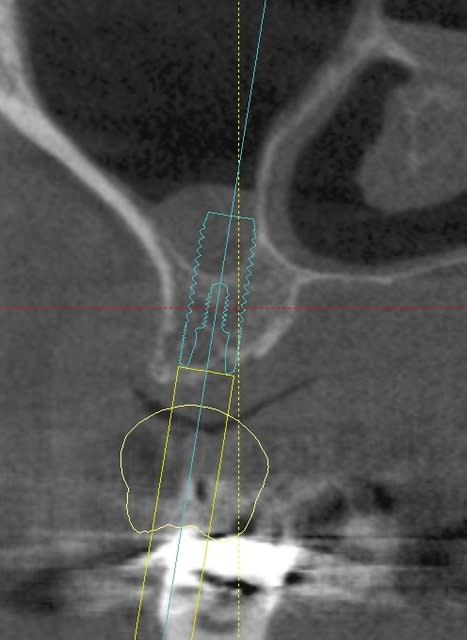

J'avais pas envie de faire un nouveau post, alors je m'incruste dans celui ci.

Vous avez déjà vu un spongieu si peu dense à la mandible?

Vous pensez que je peux donner lateralement un coup de MIS avant de mettre l'implant?

Je pense mettre un Krestal donc un peu agressif tout de m^me de 5.1 par 8.5.

çà mange pas de pain...tu fais ta prep au MIS, un coup de foret terminal...et hop...pose de l'implant...çà sera pas une expansion...mais une condensation osseuse...qui te donnera une bonne stab primaire...

condenser si tu veux, mais expanser oui, si j'avais un cas comme ça, je donnerais un coup de disque diamant sur la crête, et expansion (bone splitting) c'est le type d'os idéal pour ce genre de pratique

même pas sur d'avoir besoin du mis ou autre système rotatif, un sydesmostome conique voir un fouloir à amalgame si tu veux et tu déplace tranquillement ta paroi vestibulaire.

par contre pas un 5!

si tu veux mettre un 5 écrête et condense, mais tu aurais un meilleur résultat avec deux 3.4 sans écrêter, avec expansion.

et pourquoi un seul implant?